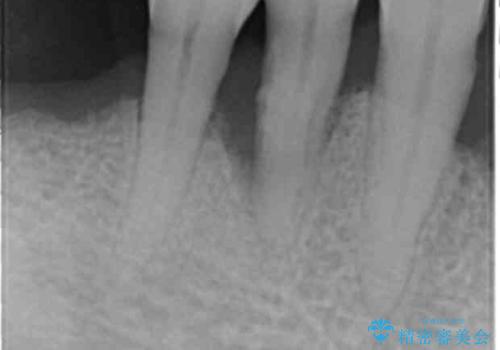

精査したところ、全顎的な重度の歯周病により右下の小臼歯(右下4)激しい動揺を認めました。

再生療法から1年後リエントリー手術により骨の再生を確認し、骨外科処置(骨を平らにして歯周ポケットの根本的な改善を図る処置)を行ったのち、連結補綴を行いました。

再生療法と骨外科処置により、歯周ポケットは全周2mm以下に改善されました。